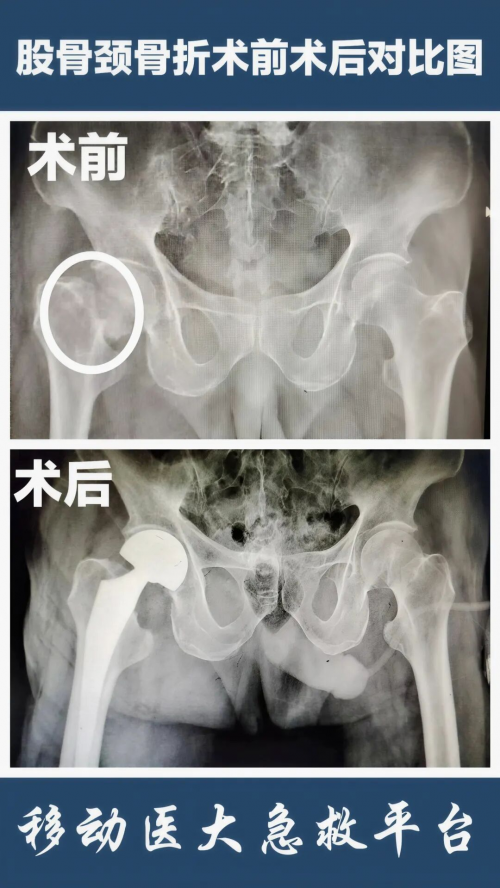

髋部骨折:多因侧翻或臀部着地摔倒引起,常见于股骨颈或股骨粗隆间骨折。髋部骨折后果严重,被称为“人生最后一次骨折”,一年内死亡率可达20%-50%,常伴有剧烈疼痛、无法站立或行走。

若老人不慎跌倒,应保持冷静,避免随意移动受伤部位,及时呼叫急救人员。骨折后需遵循医生建议进行治疗,避免长期卧床引发并发症。特别是老年股骨颈骨折,早期关节置换是关键,患者一般在术后第二天即可下地活动,有效避免因卧床引起的并发症。